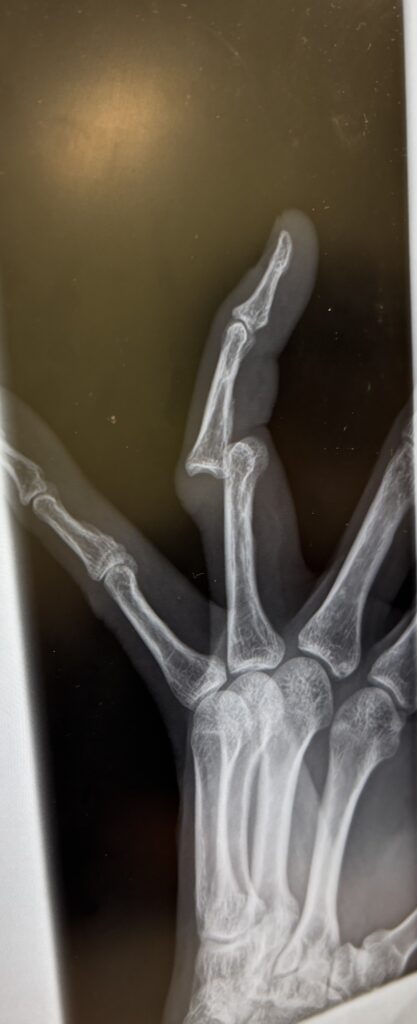

先日、レッスン中にパンチミットを持ってる際に受け損ねてミットの先の方でパンチを受けてしまいました。

ラウンド終了後、ミットを外してみると左手薬指があり得ない曲がり方をしており思わず笑ってしまいました。

しっかり握る動作や力は入れられないのと痛みがありますのでまだミットは持てませんが、来週には持てるかと思います!